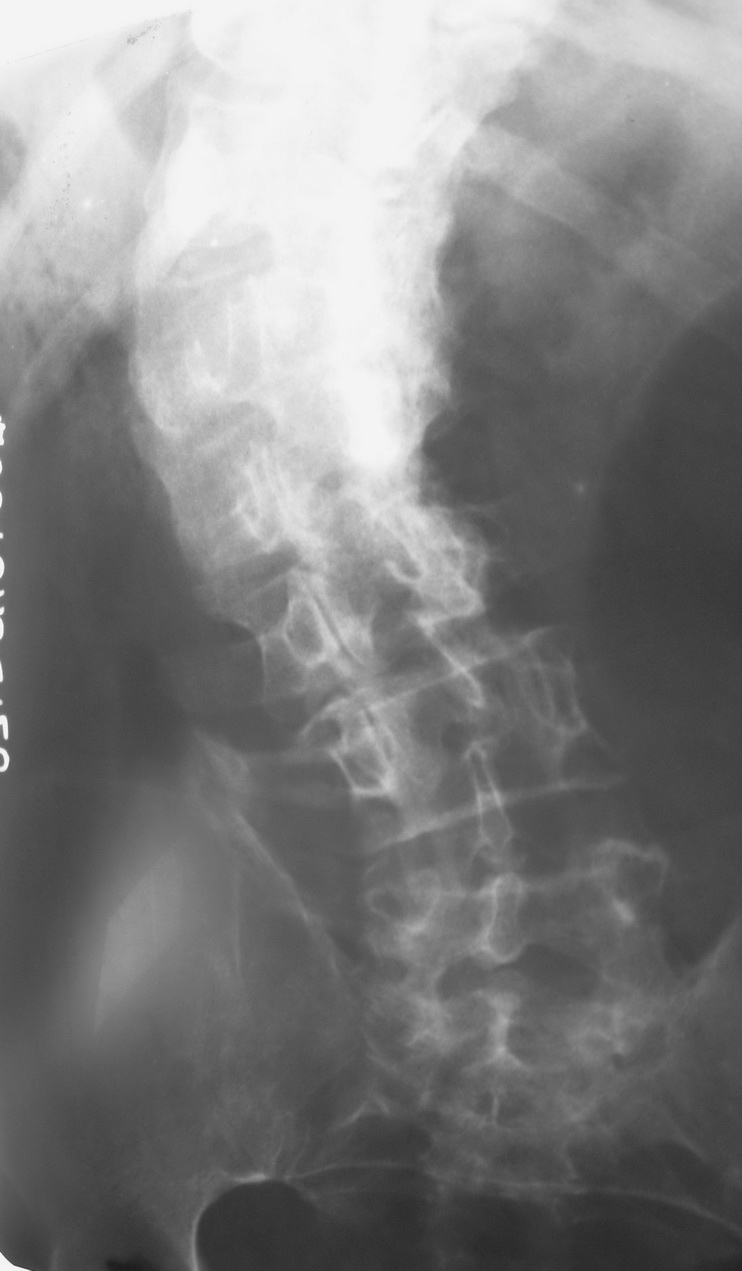

标题: X4179:腰椎会诊

请各位指点。

脊椎侧弯畸形,上面太白,看不清。

考虑:脊柱侧弯,l123看不清,可能有半椎畸形等,查查尿生殖道是否有异常.

脊柱s形侧弯旋转,t12,l1.2看不清.请提供侧位片.

显然上部腰椎已是强直性表现.病因只有结合病史.前面的老师提到畸形性骨炎, 我认为可不考虑,因为没畸形性骨炎的主要表现,即骨体呈增大增宽的破坏和成骨.

脊椎成\"s\"形弯曲,椎体边缘骨质增生改变明显,考虑脊椎侧弯畸形伴退变

脊椎成"s"形弯曲,椎体边缘骨质增生改变明显,考虑脊椎侧弯畸形伴退变